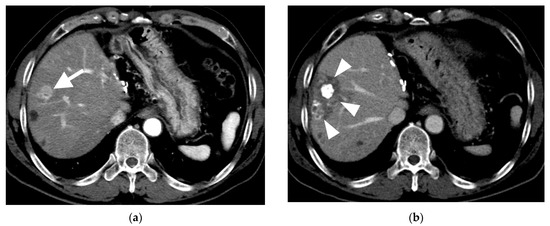

3.1. B-TACE Procedure and Complications

3.2. Follow-Up

3.3. Local Recurrence